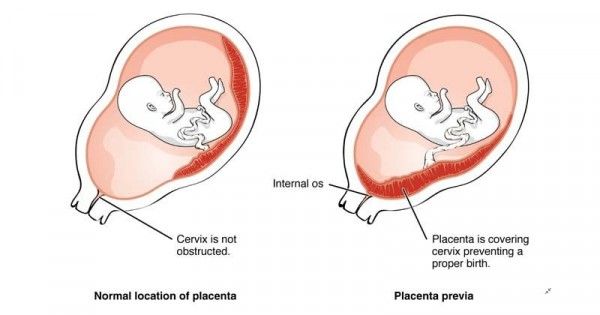

Plasenta Previa Saat Hamil, Berbahayakah? - Ibupedia

Plasenta Previa Saat Hamil, Berbahayakah? - Ibupedia

Waspadai Plasenta Previa, Bahaya Jalan Lahir Tertutup Ari-ari

Waspadai Plasenta Previa, Bahaya Jalan Lahir Tertutup Ari-ari

Waspadai Plasenta Previa, Bahaya Jalan Lahir Tertutup Ari-ari

Waspadai Plasenta Previa, Bahaya Jalan Lahir Tertutup Ari-ari